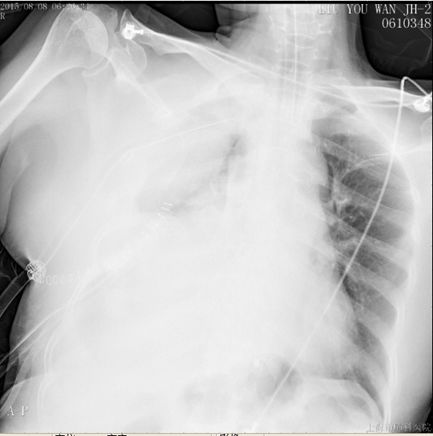

溶栓18h后,胸引量明显增多,同时提醒胸腔内大量血肿,因此于术后第五日,予以全麻下行VATS剖胸止血术,手术时间1.5h,术中失血600ml,输血球2单位,术后带气管插管入ICU。止血术后第一日胸引量450ml,复查血气正常,予以拔除气管插管,SPO2 96%,HR 81bpm,BP 135/88mmHg。

之后转入肺循环科继续抗凝治疗,住院总天数33天。

出院用药及随访

出院时情况:CTPA未见充盈缺损,下肢静脉彩超提示无血栓。血常规、凝血功能、肝、肾功能等无变化,患者一般情况可予以出院。